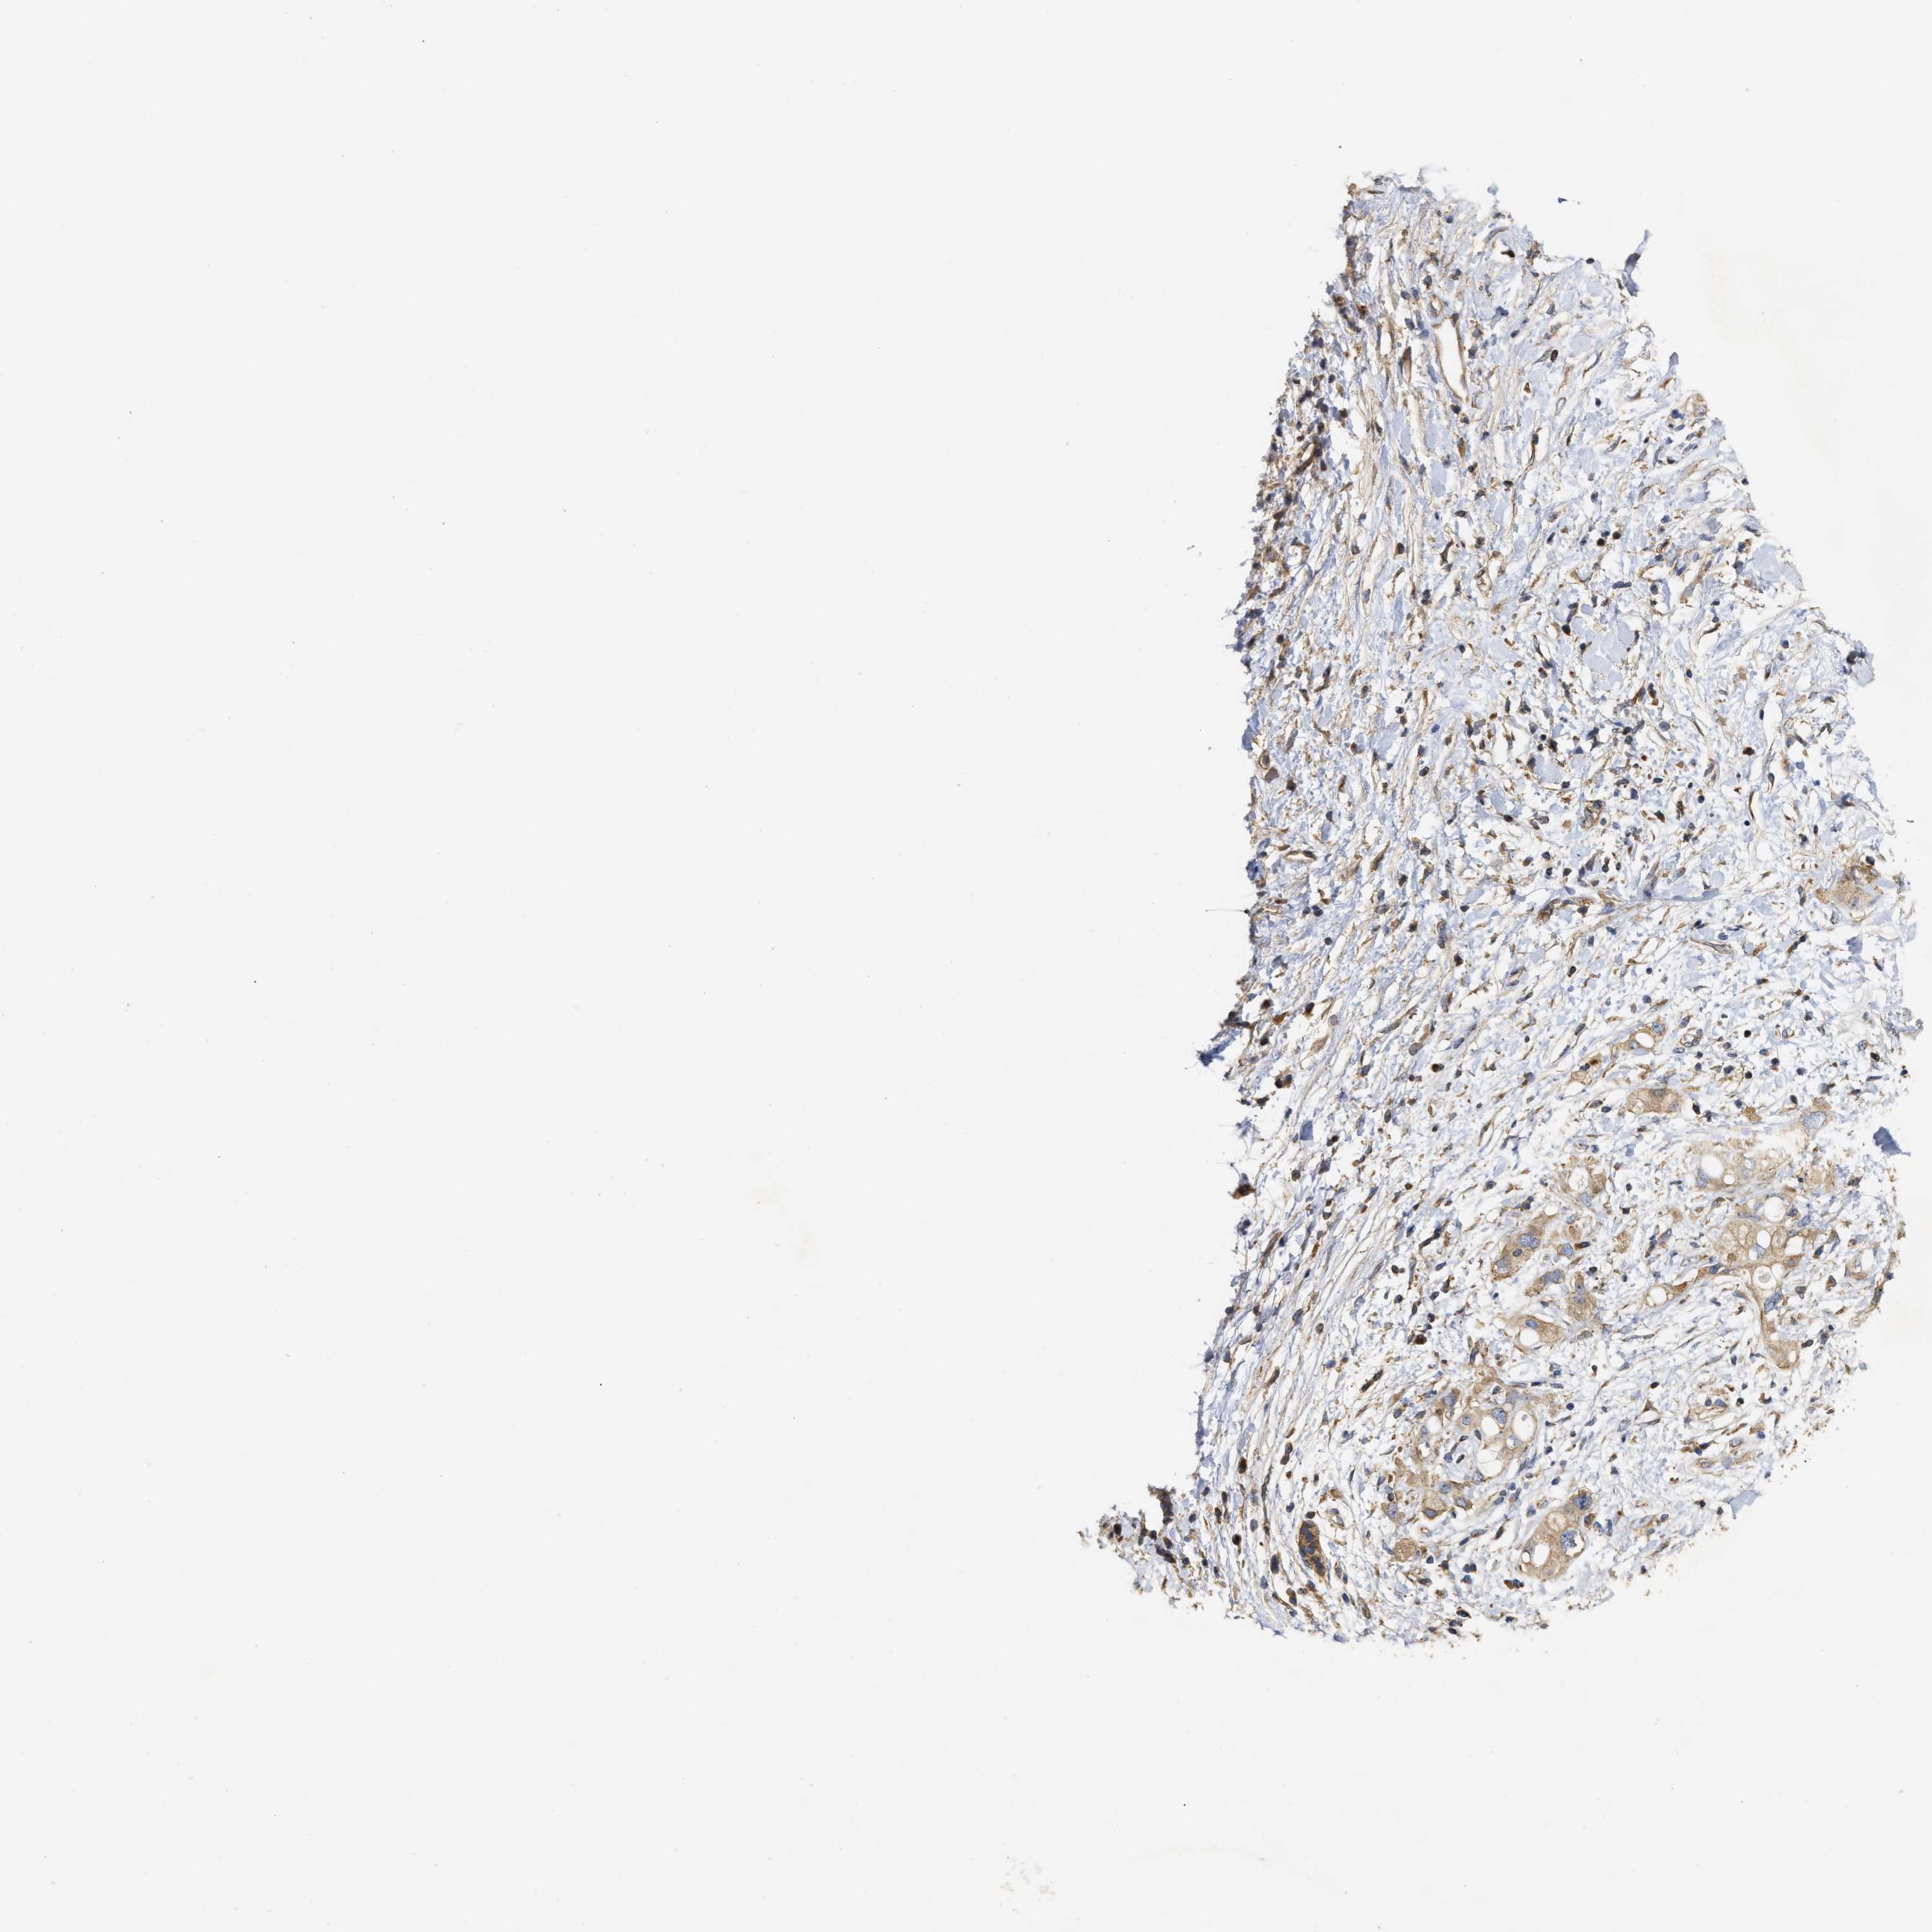

PANCREATIC CANCER - Protein expressioni

A mouse-over function shows sample information and annotation data. Click on an image to view it in a full screen mode. Samples can be filtered based on level of antibody staining by selecting one or several of the following categories: high, medium, low and not detected. The assay and annotation is described here.

Note that samples used for immunohistochemistry by the Human Protein Atlas do not correspond to samples in the TCGA dataset.

Antibody stainingi

Antibody staining in the annotated cell types in the current human tissue is reported as not detected, low, medium, or high, based on conventional immunohistochemistry profiling in selected tissues. This score is based on the combination of the staining intensity and fraction of stained cells.

Each image is clickable and will lead to virtual microscopy that enables deeper exploration of all samples and also displays staining intensity scores, fraction scores and subcellular localization as well as patient and tissue information for each sample.

Antibody HPA018127

Antibody HPA027887

Antibody CAB012302

Adenocarcinoma, NOS

Adenocarcinoma, metastatic, NOS